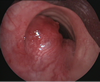

Patología tráqueo-bronquial